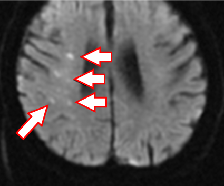

散在性脳梗塞(MRI)

もやもや病

頭蓋内血管の閉塞がみられます。血管造影では血管が閉塞し、周囲に「もやもや病」がみられます。

バイパス手術によって血管が頭蓋骨を通り、皮膚の太い血管と脳をつなげて治療します。

もやもや病のMRA画像

血管造影検査の画像

バイパス術後のCTA画像